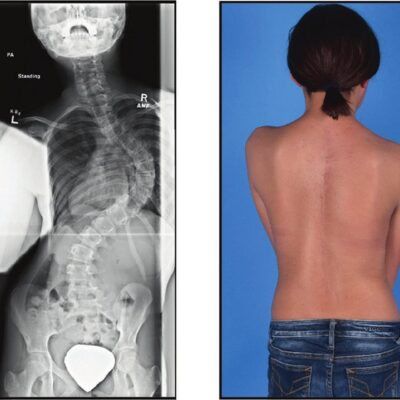

Escoliosis Costilla Sobresaliente: Cómo abordar el problema de las costillas sobresalientes debido a la escoliosis y opciones de tratamiento

Scoliosis, a condition characterized by an abnormal curvature of the spine, can often lead to [...]

Escoliosis de la Caja Torácica Desigual: Manejo y tratamiento de la deformación de la caja torácica causada por la escoliosis

Uneven Rib Cage Scoliosis is a comprehensive guide that delves into the management and treatment [...]